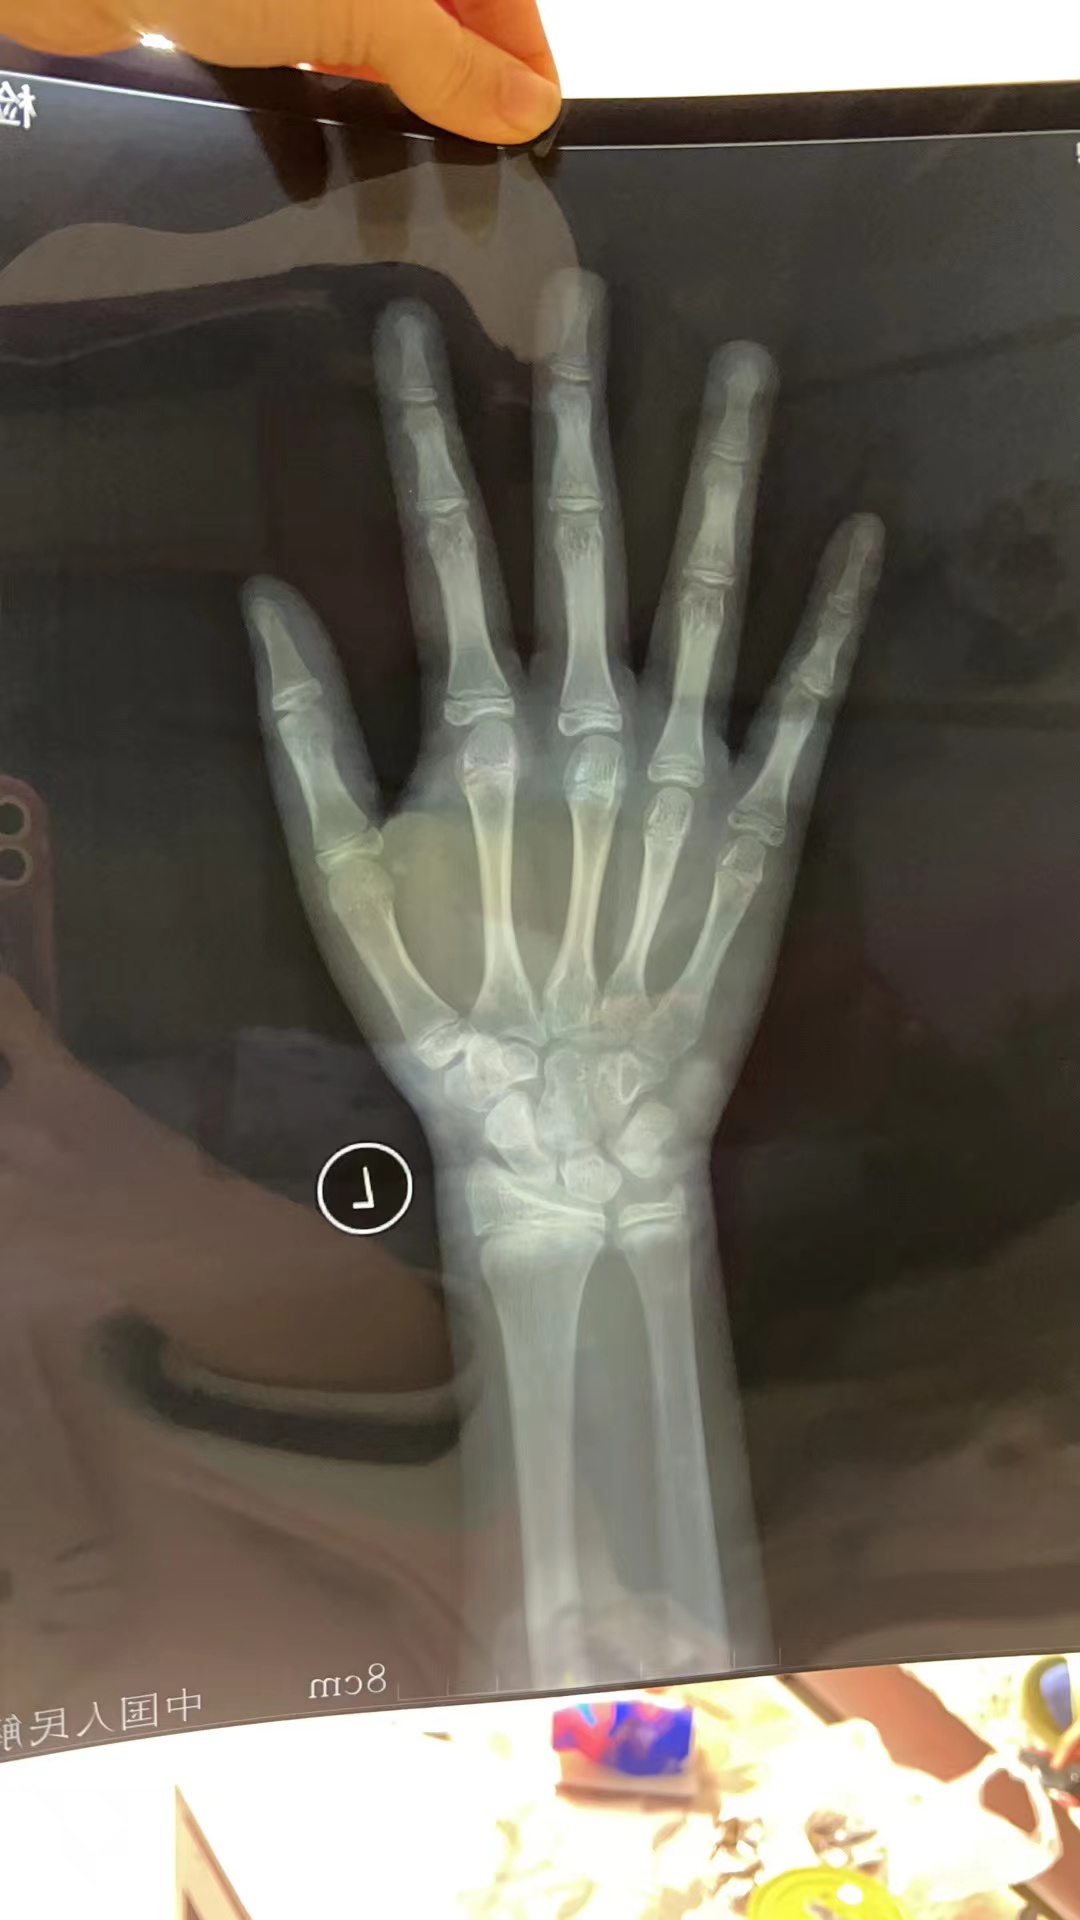

有没有大神帮忙看看孩子的骨龄,今年9岁.来例假了. 身高目前1.

图片尺寸1080x1920